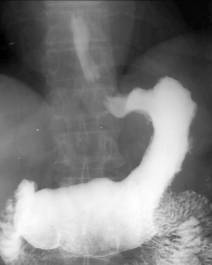

Imagistic, polipii apar ca formatiuni rotunde de dimensiuni variabile, bine delimitate, legate de peretele gastric printr-un pedicol mai lung care îi confera mobilitate, sau mai larg si scurt (polip sesil)-fig.189. Când se afla în antrul prepiloric, polipul poate prolaba în bulbul duodenal.